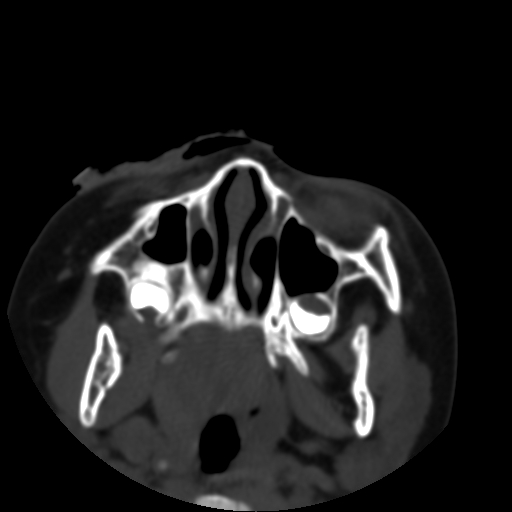

以下是引用深泽交通医院在2009-10-16 8:25:00的发言:[br]右眼环出血伴异物

以下是引用拾荒者在2009-10-17 18:38:00的发言:[br]鼻面部皮下积气,右侧睑缘及眼球壁高密度异物影,左侧眼球壁晶状体内侧缘处是圆形低密度影。低密度异物?应提请眼科医生注意。